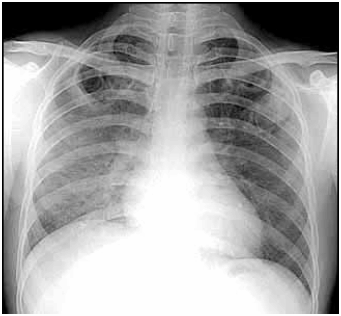

Com base na radiografia abaixo, assinale a alternativa correta:

A

Trata-se de uma radiografia do abdome em decúbito.

B

Trata-se de uma radiografia de tórax, perfil, apresentando Atelectasia.

C

Foi e deve ser feita com alta quilovoltagem e baixa mAs.

D

Foi e deve ser feita sem grade.

E

Trata-se de uma radiografia de tórax, perfil, apresentando esôfago opacificado.